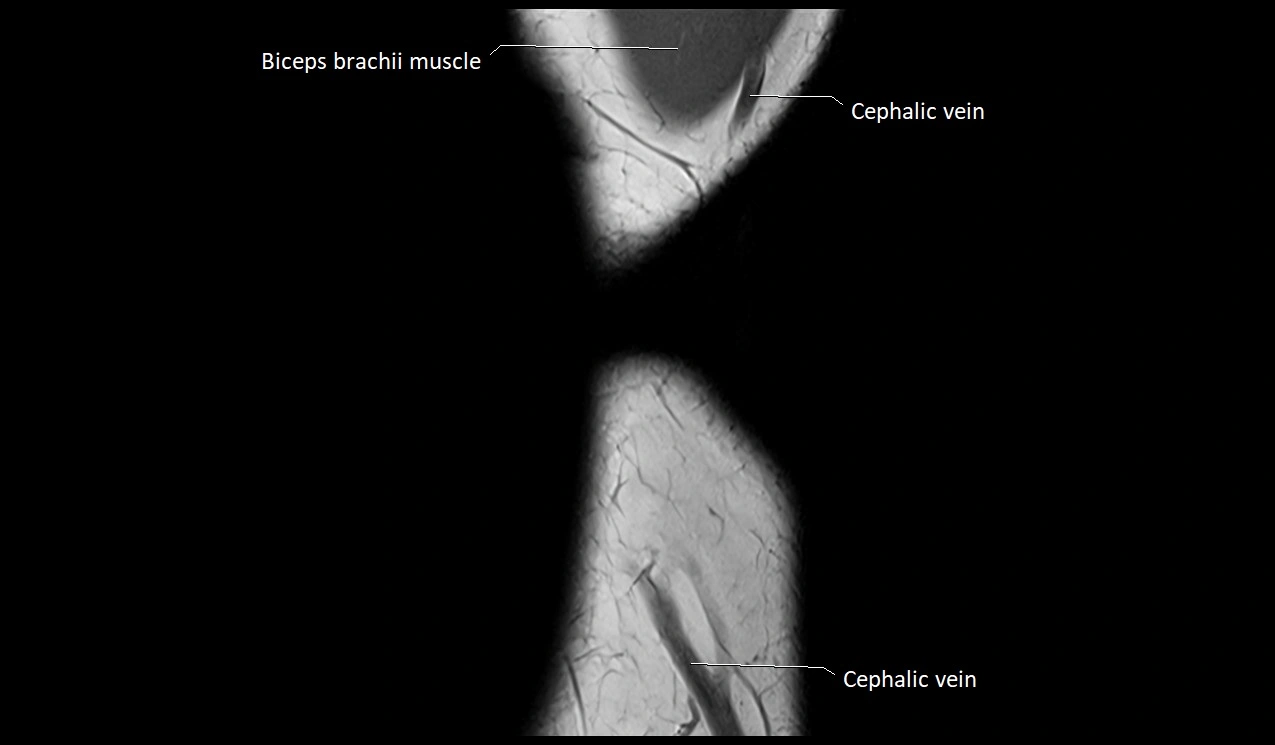

MRI image

image